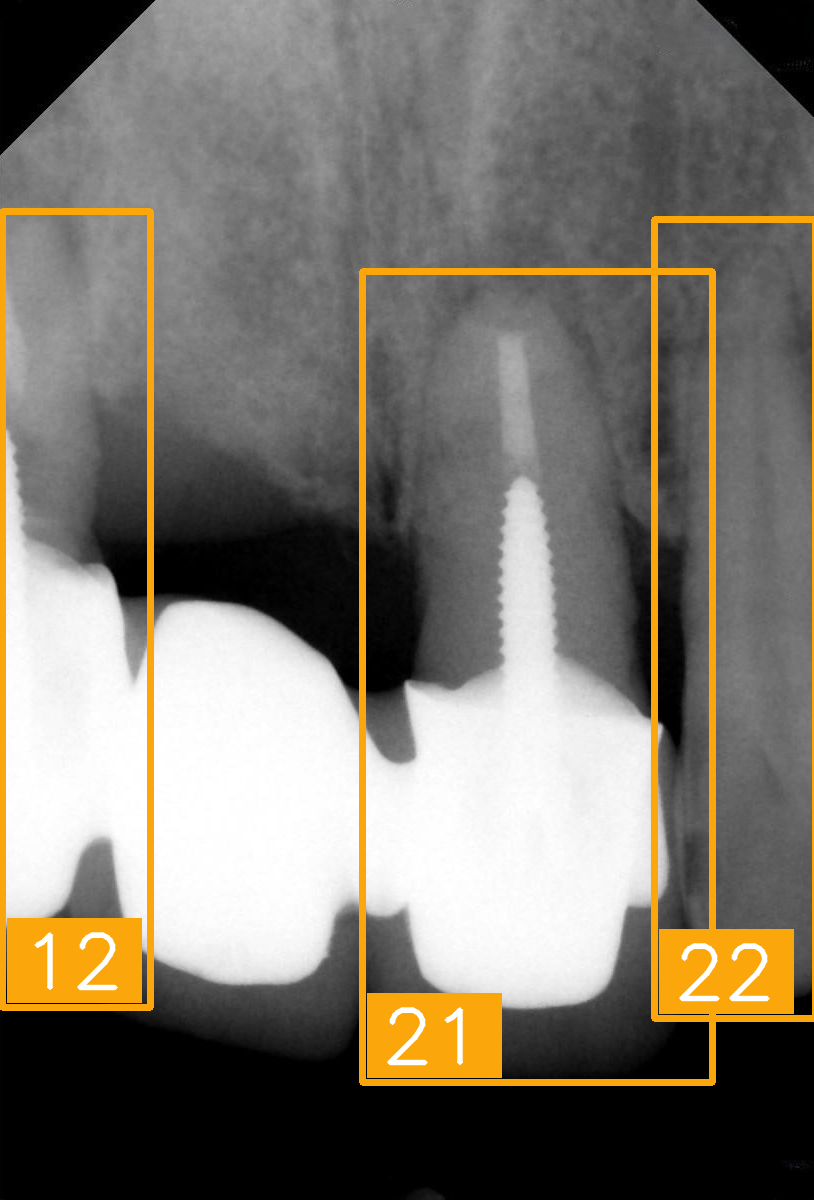

| Number | (a) | (b) | (c) | (d) |

| Condition | Fractured tooth; Implant | Overlaapping | Missing Tooth | Incomplete crown |

| PA | ![]() | ![]() | ![]() | ![]() |

| FDI ground truth number | 23, 24, 25, 26 | 43, 42, 41, 31, 32, 33 | 12, 11, 21, 22 | 44, 43, 42, 41, 31, 32 |

| Inference Time | 75.9 ms | 73.3 ms | 76.1 ms | 69.9 ms |